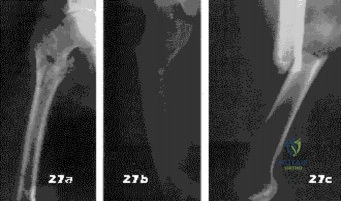

- Ewing’s sarcoma

- Osteogenic sarcoma

- Multiple myeloma

- Metastatic prostate carcinoma

- Metastatic breast carcinoma

- Ewings tumor

- Parosteal osteosarcoma

- Dedifferentiated chondrosarcoma

- Low grade intramedullary chondrosarcoma

- High grade intramedullary osteosarcoma